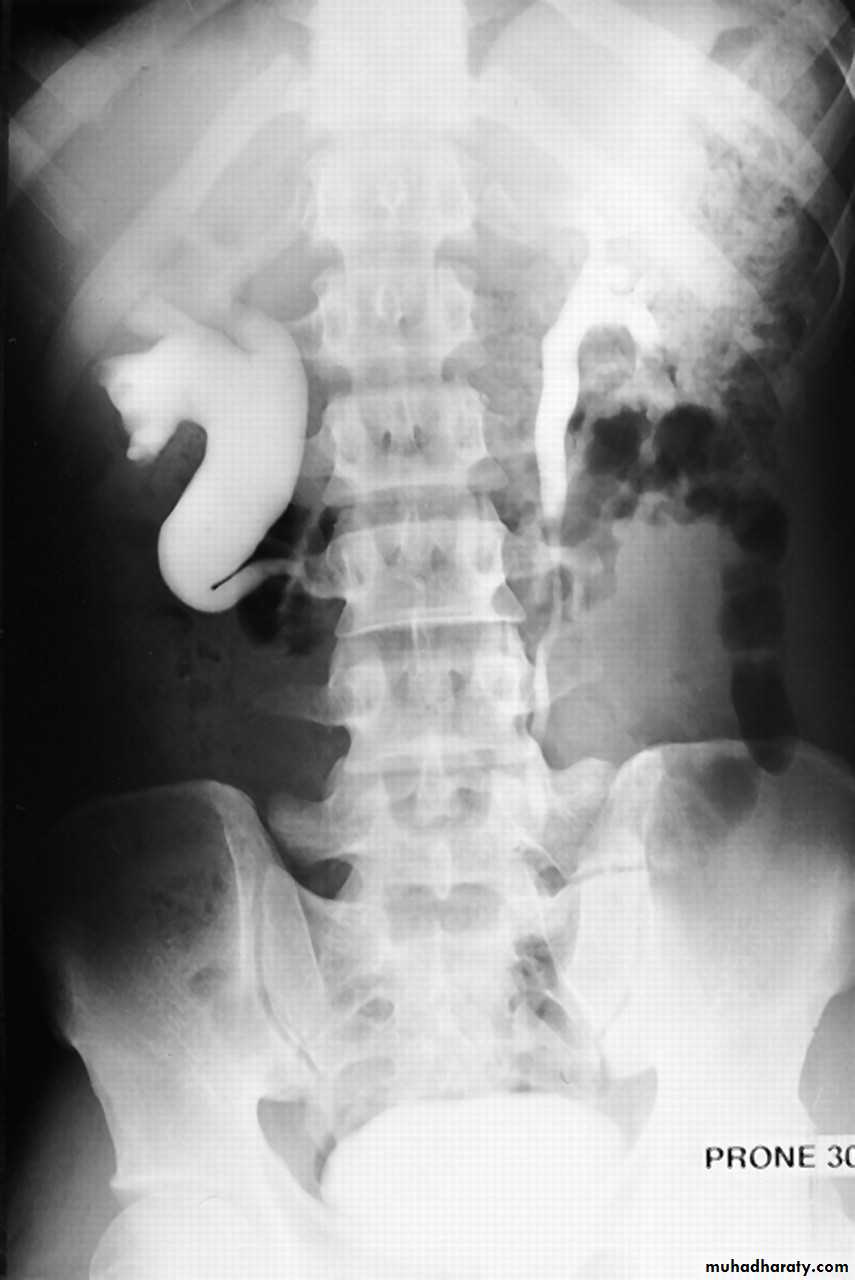

12- Bilateral megaureter